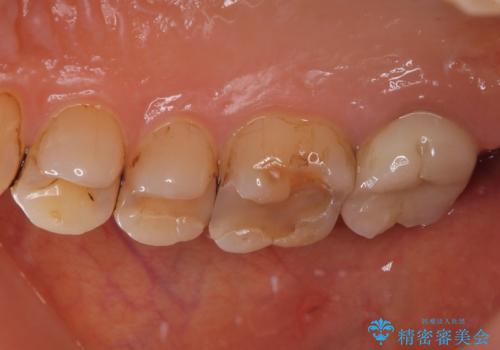

拡大鏡視野下で古い被せものを除去し、オールセラミッククラウンに適した形に整えました。

歯と歯茎の間に圧排糸と言われる糸を入れてシリコーン印象材にて型どりをしました。

患者様のご希望により、根管治療、土台のやり替えは行っていません。